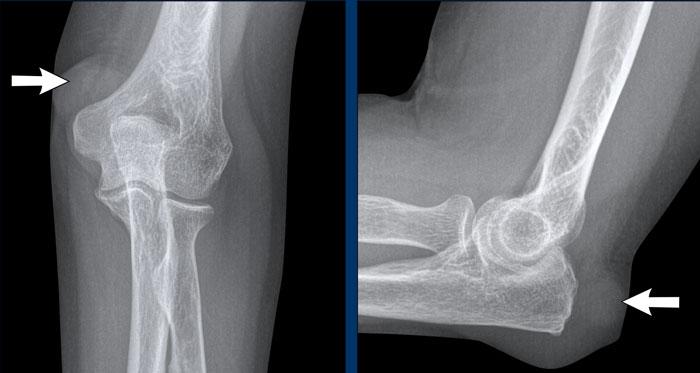

Nốt dạng thấp

Nốt dạng thấp là các cục cứng xuất hiện dưới da ở tới 20% bệnh nhân viêm khớp dạng thấp.

Các nốt này thường xuất hiện liền kề với các khớp bị lộ ra ngoài, dễ bị chấn thương hoặc chịu áp lực, chẳng hạn như các khớp ngón tay và khuỷu tay.

Trong thể bệnh này của viêm khớp dạng thấp, thường không có bất thường tại khớp.

Hình ảnh

Khối phần mềm (tức là nốt dạng thấp) trong lớp mô dưới da ở mặt lưng – bên ngoài của mỏm khuỷu.